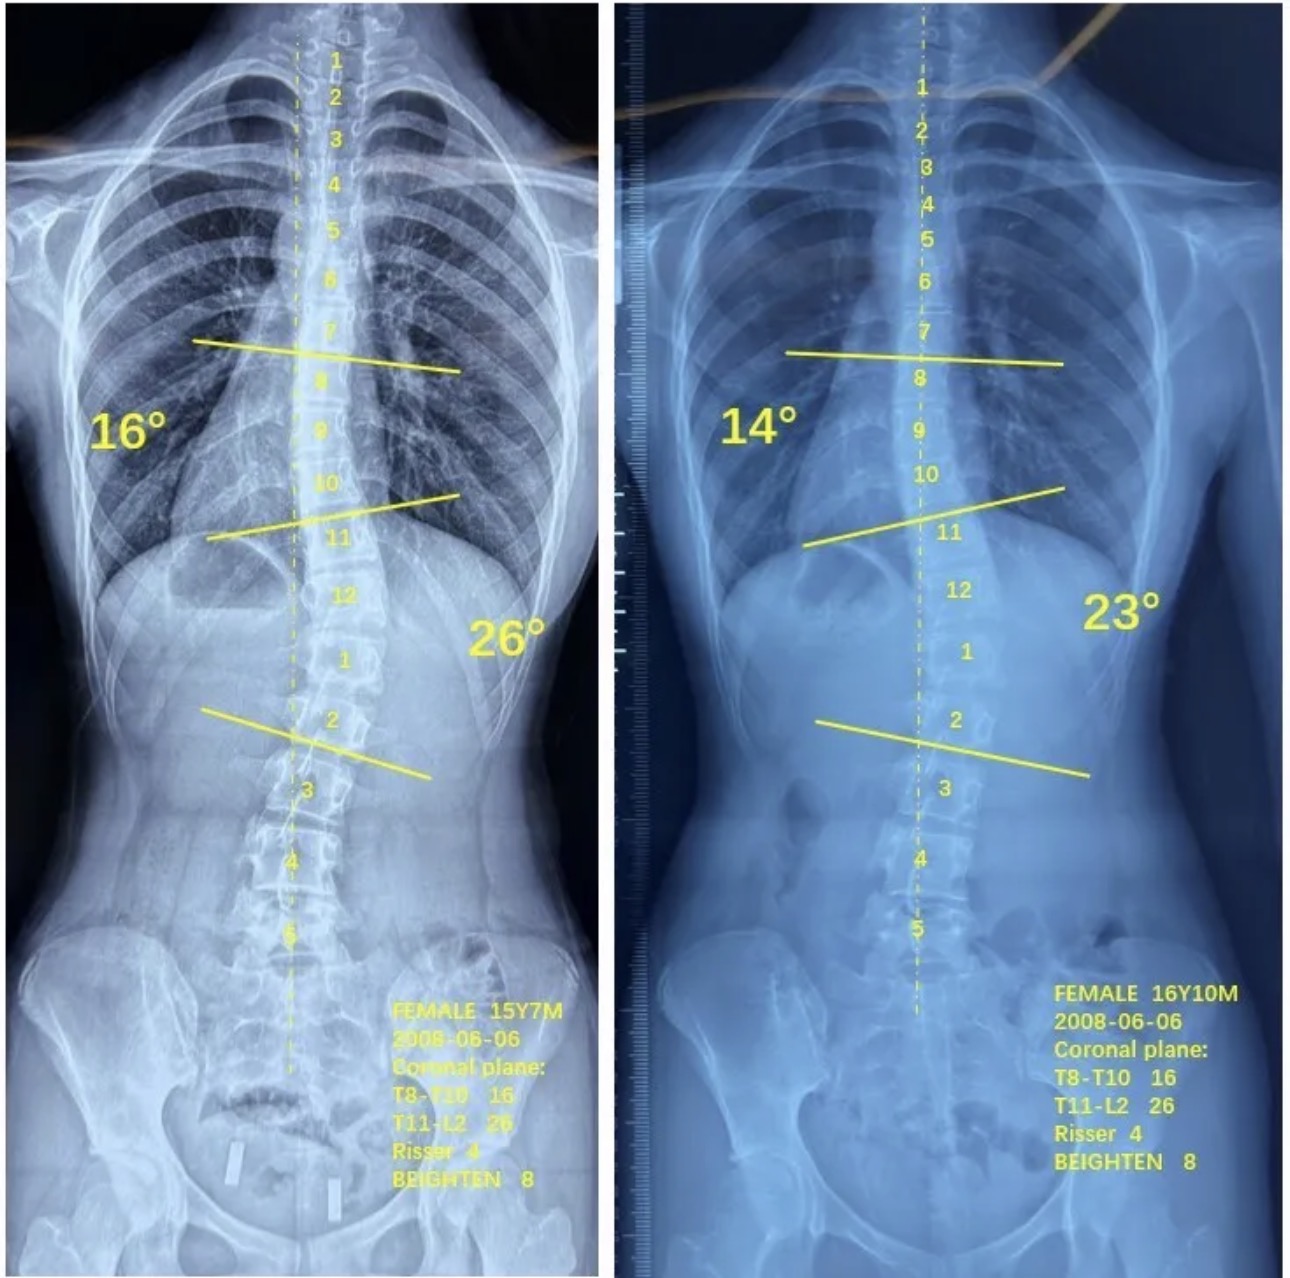

衷德脊柱,我们只关注侧弯保守治疗~

Zhongde Spine, bending no breaking ~